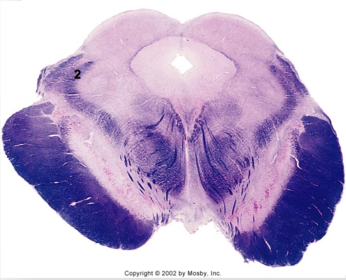

| Longitudinal pontine fibers (corticospinal tract) | |

| Transverse pontine fibers (dark fibers) | |

| Pontine nuclei (pale) | |

| Medial lemniscus | |

| ALS | |

| Trapezoid body | |

| Ventral trigeminothalamic tract | |

| Superior olive | |

| Central tegmental tract | |

| Facial nerve root fibers - descending | |

| Facial motor nucleus | |

| Interposed nuclei | |

| Medial longitudinal fasciculus | |

| Facial nerve root - internal genu | |

| Abducens nucleus | |

| Lateral vestibular nucleus | |

| Superior vestibular nucleus | |

| Inferior cerebellar peduncle | |

| Superior cerebellar peduncle | |

| Dentate nucleus | |

| Fastigial nucleus | |

| Anterior spinocerebellar tract | |

| Spinal nucleus of V | |

| Spinal tract of V | |

| Middle cerebellar peduncle | |